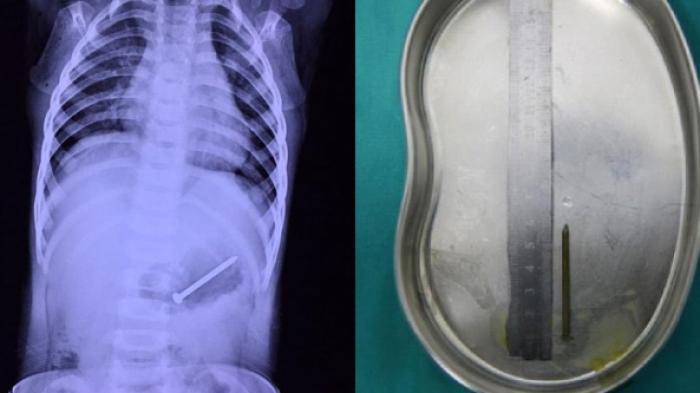

POSBELITUNG.COM, TIONGKOK - Seorang nenek di provinsi Jiangxi, Tiongkok terkejut setelah mendapati cucunya yang baru berusia 1 tahun menelan paku sepanjang 5 cm dan bersarang di perutnya.

Hingga akhirnya kecurigaan mulai terjawab oleh hasil ronthgen atau X-ray.

Benar saja gambar tersebut menujukan paku itu bersarang di perut sang cucu.

South.cn melaporkan bahwa X-ray menunjukkan bahwa paku itu sebenarnya terletak di perut anak itu.